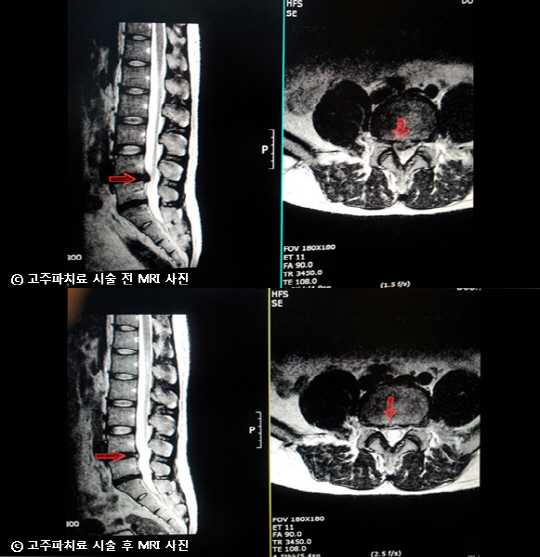

비수술의 첫 번째 경우가 주로 목과 허리디스크에에 시술되는 고주파 치료다. 일반적으로 고주파 치료는 고열로 디스크 주변을 녹여 압력이 줄어들도록 하는 고주파 디스크 감압술이 활용된다. 그러나 박 원장은 디스크 주변이 아닌, 튀어 나온 디스크를 직접 공략하는 '플라즈마 디스크 열 응고술'로 시술한다. 아주 정교한 시술로서 고도의 테크닉이 필요하기 때문에 시도 하는 병원은 드물다.

일반적으로 디스크 주변을 녹여 압력을 없애는 '감압술'은 터져버린 디스크가 원래 자리로 돌아오지 않아 성공률이 크게 보장되지 않는다. 반면 신경을 압박하고 있는 디스크를 직접 제거하여 완쾌율을 높이고 있다. 박 원장은 연세의대 강남세브란스 병원 척추센터 전임의 과정과 강남베드로병원 척추센터장을 거쳤다.